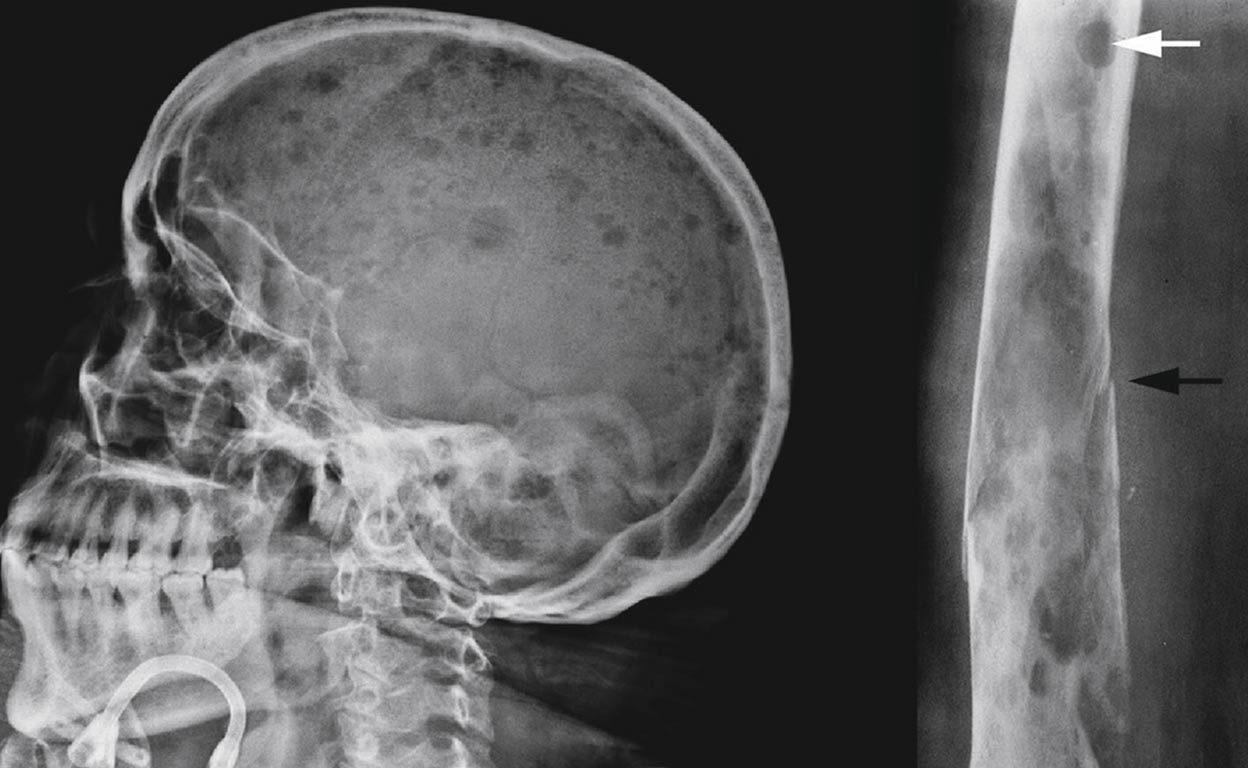

alternative text

En proceso. Emma Whitehead en abril de 2012 durante su tratamiento en el hospital infantil de Filadelfia.